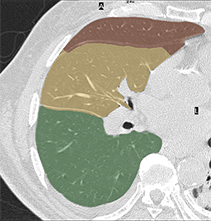

![]() |

| (a) initial seeds | (b) Potts model |

| (c) Potts model | (d) Hedgehogs + Potts |

| (c) Multi-Star + Potts model | (d) Hedgehogs + Potts model |

For the example shown in Fig.9(a), (b-c) show Potts model results for and 6, respectively. It should be noted that is the smallest smoothness weight that did not result in over-segmentation when using Potts. However, the result in Fig.9(c) is biased towards smaller objects (notice star tips) because by increasing the smoothness weight we are also increasing the shrinking bias. Over-segmented results as the one in Fig.9(b) could be avoided without increasing the shrinking bias, simply by incorporating multi-shape priors. Our method which incorporates Hedgehogs shape priors with Potts model was able to find a better segmentation, see Fig.9(d).

The objective of the example shown in Fig.10(a) is to segment left and right lungs, and the background. Potts model result shown in Fig.10(b) has holes, i.e. part of the background appears in the middle of the lungs. Furthermore, Potts model converged to biased color models where the right lung preferred brighter colors while the left preferred darker colors. Similar to the previous example, increasing for Potts model will increase the shrinking bias and it becomes hard to segment the elongated part of the the right lung. Using multi-star which is a generalization of [25] to multi-object segmentation is not enough because the right lung is not a star-shape. To be specific, there is no point inside the right lung that could act as a center of a star-shape that would include it. Fig.10(d) shows the result for our method, where user scribbles were used to enforce shape constraints compared to using a single pixel per label [9].